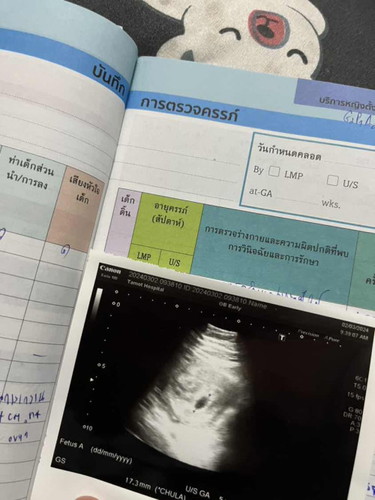

ตอนแรกนับตามประจำเดือน 9วีคแล้วค่ะ แต่วันนี้มีเลือดออก เลยไปหาหมอ หมอซาวไห้ พบแค่ถุงตั้งครรภ์ อายุครรภ์แค่5วีคเองค่ะ รูปนี่คือเลือดออกมารอบ2แล้วค่ะ